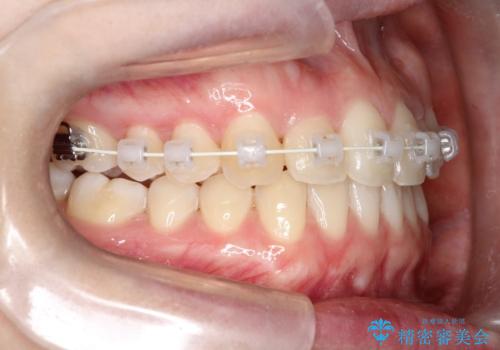

インビザラインとワイヤー矯正の併用で綺麗な歯並びに!

- インビザライン、ワイヤー矯正

- 前歯のガタツキが気になるとのことで来院されました。

ワイヤー矯正とインビザライン矯正を併用することによって、治療期間の短縮と、より良い仕上がりを目指す治療を選択することとしました。

インビザライン(アライナー)矯正とワイヤー矯正のそれぞれの利点を生かした治療を行い、綺麗な歯並びになりました。